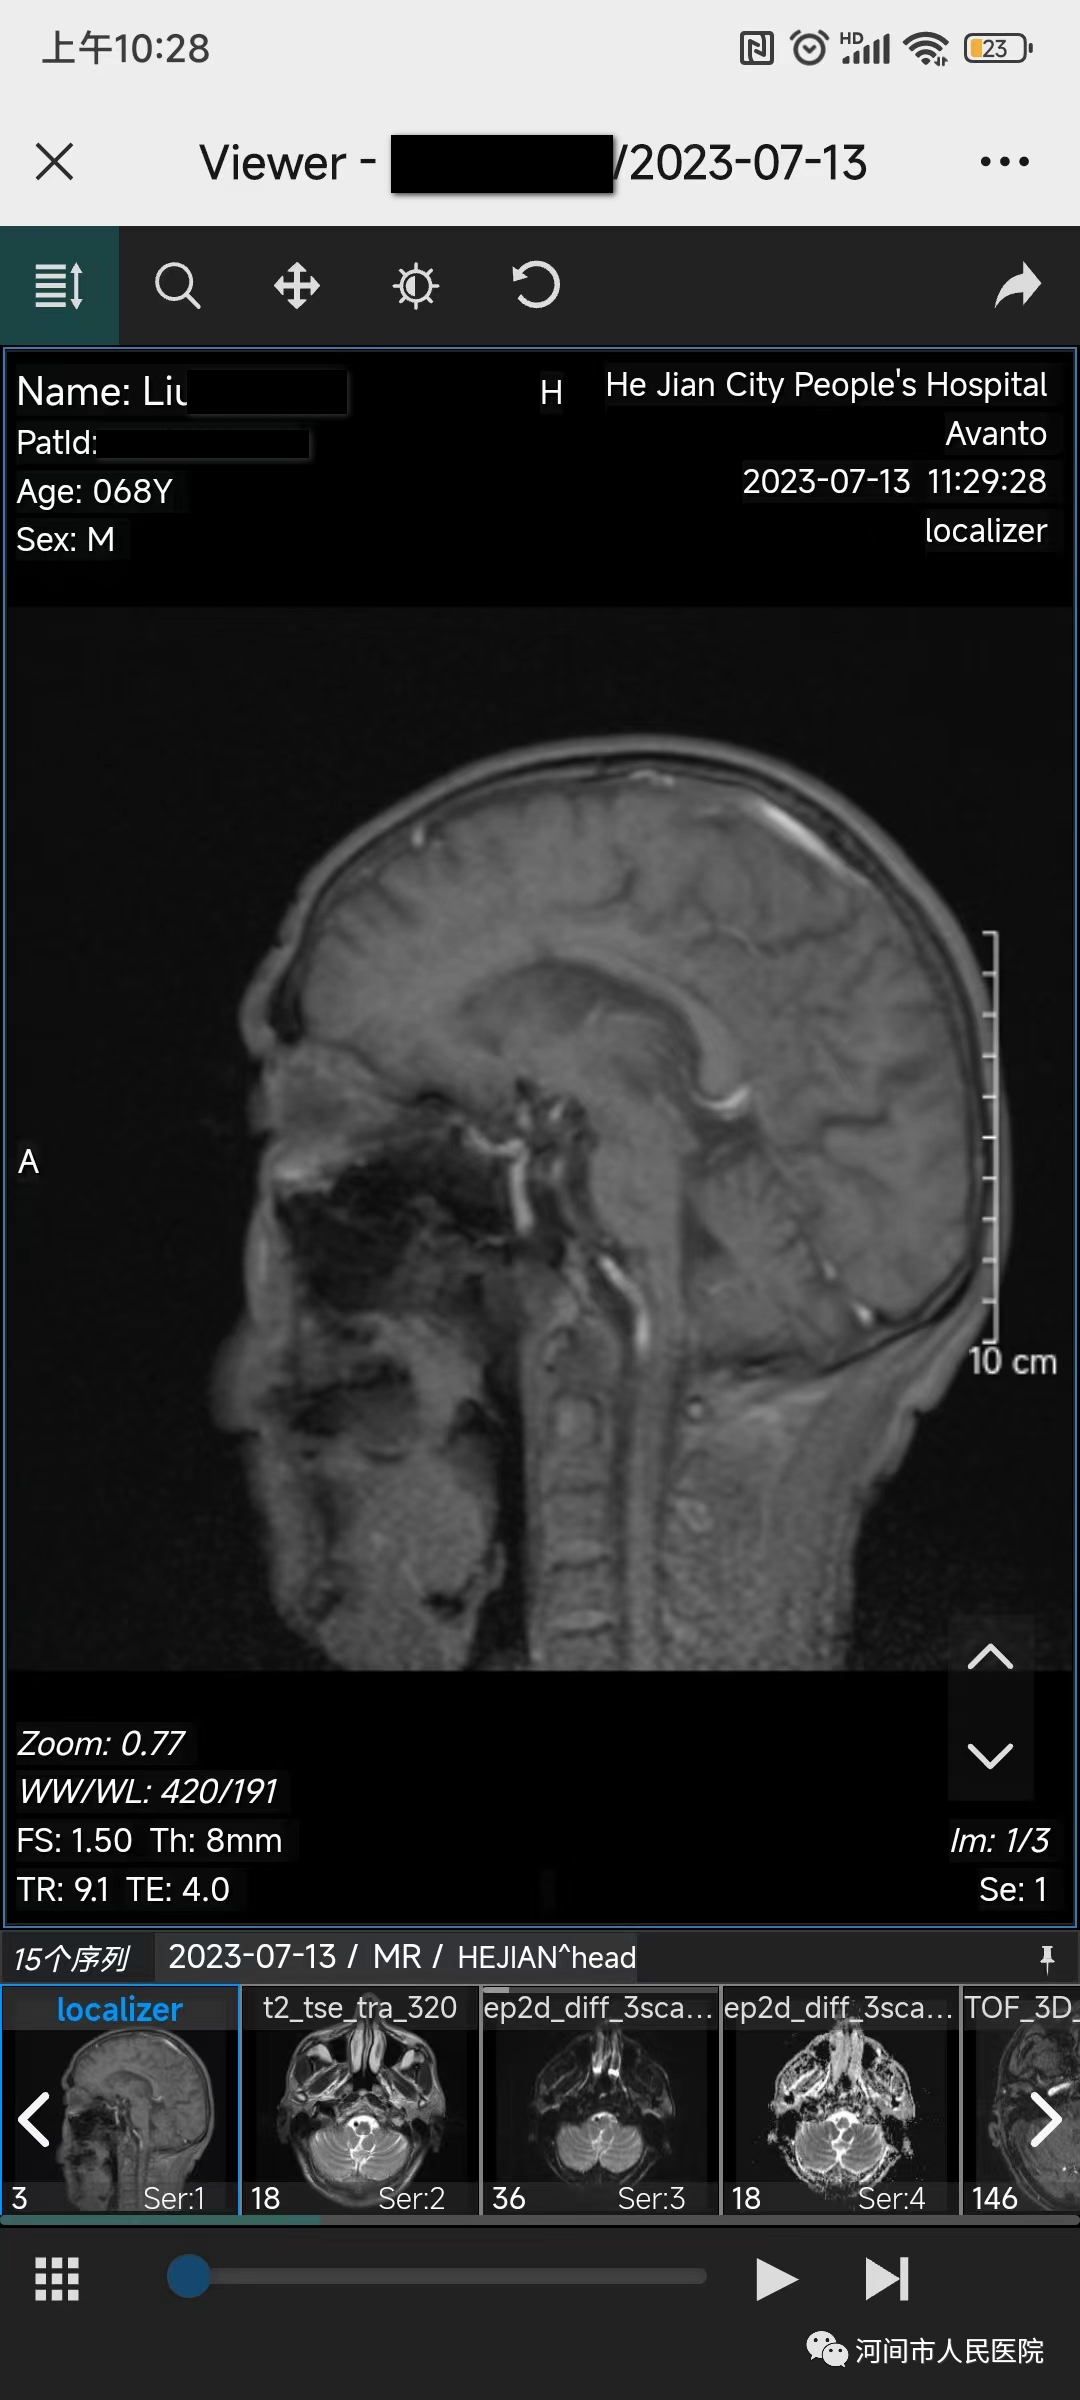

醫院在開展影像檢查時,將DICOM格式圖片存儲(chu) 在影像雲(yun) 平台上,患者可通過掃描二維碼隨時在手機上進行調閱、下載影像(磁共振、CT、放射)檢查結果。

1、就診更便捷。患者在做完相應的影像學檢查後,在手機上可隨時查詢影像檢查結果,無需往返醫院取片,減少患者往返醫院次數。

2、診斷更精確。手機影像雲(yun) 可提供完整的原始影像數據,也可查詢已上傳(chuan) 到影像雲(yun) 平台所有曆史影像數據,醫生可分析對比前後檢查的影像結果,做出更科學、更精確的診斷。

3、分享更方便。如需要遠程會(hui) 診,可通過微信分享二維碼,專(zhuan) 家可查看原始影像,不需要長途奔波,更省時省錢。